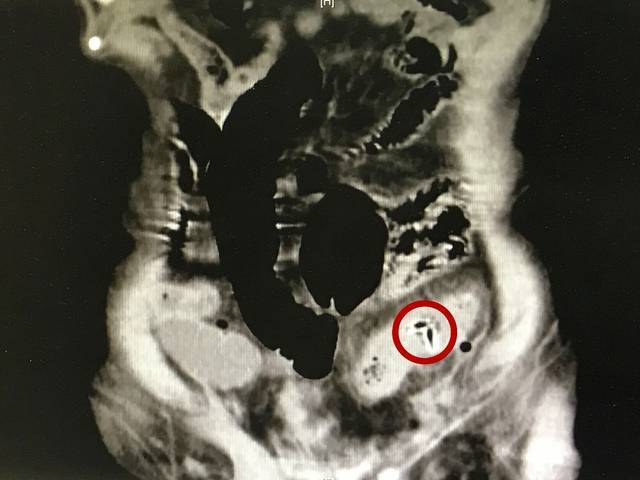

图中红圈所示为枣核

张鹏说,吃枣的人很多,毕竟被送进急诊的人是少数,但每年因为异物划破肠道来就诊的人,大部分都是因为枣核。枣核比较硬、两头尖利,很容易扎破食道或肠壁,非常危险。在八宝粥、枣糕里面可能有枣核,但最多的情况还是一不小心在吃枣的时候咽下去的。因此,吃枣时一定要细嚼慢咽,不要吞食枣核。